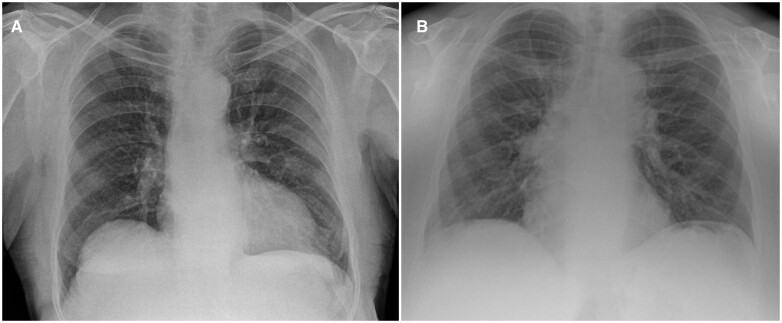

Objectives: Artificial intelligence (AI) enabled devices may be able to optimize radiologists' productivity by identifying normal and abnormal chest X-rays (CXRs) for triaging. In this service evaluation, we investigated the accuracy of one such AI device (qXR).

Methods: A randomly sampled subset of general practice and outpatient-referred frontal CXRs from a National Health Service Trust was collected retrospectively from examinations conducted during November 2022 to January 2023. Ground truth was established by consensus between 2 radiologists. The main objective was to estimate negative predictive value (NPV) of AI.

Results: A total of 522 CXRs (458 [87.74%] normal CXRs) from 522 patients (median age, 64 years [IQR, 49-77]; 305 [58.43%] female) were analysed. AI predicted 348 CXRs as normal, of which 346 were truly normal (NPV: 99.43% [95% CI, 97.94-99.93]). The sensitivity, specificity, positive predictive value, and area under the ROC curve of AI were found to be 96.88% (95% CI, 89.16-99.62), 75.55% (95% CI, 71.34-79.42), 35.63% (95% CI, 28.53-43.23), and 91.92% (95% CI, 89.38-94.45), respectively. A sensitivity analysis was conducted to estimate NPV by varying assumptions of the prevalence of normal CXRs. The NPV ranged from 88.96% to 99.54% as prevalence increased.

Conclusions: The AI device recognized normal CXRs with high NPV and has the potential to increase radiologists' productivity.